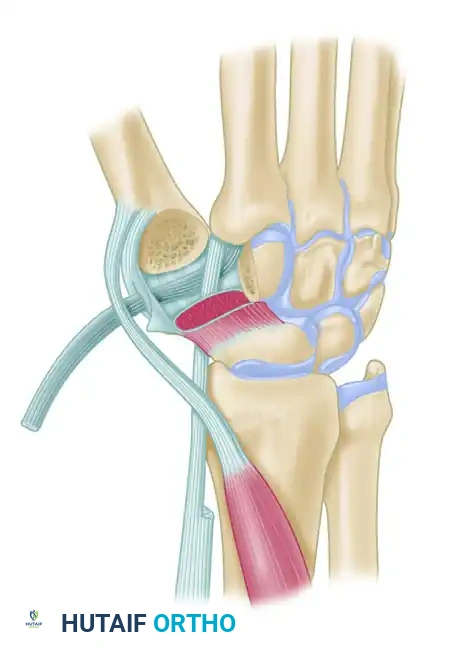

The trapeziometacarpal (TMC) joint of the thumb is a highly specialized biconcave saddle joint that affords the thumb its unique wide range of motion, including flexion, extension, abduction, adduction, and opposition. However, this mobility comes at the cost of inherent osseous instability. The primary static stabilizer of the TMC joint is the anterior oblique ligament (AOL), also known as the volar beak ligament.

Attenuation or traumatic rupture of the AOL leads to dorsal and radial subluxation of the first metacarpal base under the deforming forces of the abductor pollicis longus (APL) and adductor pollicis. Over time, this altered kinematics results in eccentric cartilage wear, volar beak osteophyte formation, and progressive osteoarthritis.

Trapeziometacarpal ligament reconstruction, originally popularized by Eaton and Littler, aims to restore the stabilizing function of the AOL using a distally based strip of the flexor carpi radialis (FCR) tendon. For more advanced disease, modifications such as the Calandruccio ligament reconstruction and tendon interposition (LRTI) or distraction arthroplasty are indicated.

- FCR Tunnel Identification: Deep dissection at the proximal border of the trapezium reveals a sheet of transverse fascial fibers. These fibers form the roof over the separate fibro-osseous tunnel of the FCR. This tunnel is separated from the main carpal tunnel by a vertical septum located between the FCR and the flexor pollicis longus (FPL).

Figure: Schema of ligament support. The key volar ligament is a reflection of the transverse carpal ligament after insertion into the crest of the trapezium. Note the FCR passing directly beneath this ligament.

- FCR Release: Incise the reflection of the transverse carpal ligament longitudinally to expose the FCR tendon. The tendon disappears distally beneath a horizontal trapezial ridge projection. Free the tendon approximately 0.5 cm distal to this point by sharp release of the overlying muscle origins.

- Metacarpal Tunnel: Create an extraarticular bone tunnel from the dorsal base of the metacarpal to the volar beak apex.

- Rerouting: Continue the split 5 mm distal to the crest of the trapezium. Redirect the free end of the tendon strip across the crest to enter the volar portion of the previously created intramedullary channel at the thumb metacarpal beak.

- Passage: Draw the tendon dorsally through the metacarpal tunnel using a previously placed wire loop or suture passer.

- Bone Tunnel Creation: Using a 4-mm rough burr, create holes through the base of the thumb metacarpal, directing them proximally and radially. Connect these holes using a series of curets (usually up to a No. 2) to form a smooth, continuous tunnel.

- Tendon Passage: Pass the harvested FCR tendon strip through the newly created bone tunnel. Hold the tendon perpendicular to the index metacarpal shaft.

- Suspension: Approximate the index and thumb metacarpal bases by applying slight ulnarly directed pressure on the thumb metacarpal. Firmly secure the FCR tendon to the APL bony insertion using 2-0 braided nonabsorbable sutures. This step acts as a "suspensoplasty," preventing proximal migration of the thumb metacarpal.

- Intermetacarpal Securing: Pass the FCR tendon between the thumb and index metacarpal bases and secure it to itself with the same nonabsorbable suture.